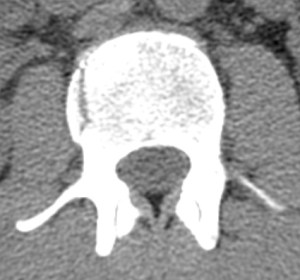

Cross section of my L2 vertebrae

Just before signing my discharge papers the doctor came in and put an end to the fun. He said that a more senior radiologist looked at the X-ray of my back and spotted a compression fracture in my L2 vertebrae. My response: “you’re shitting me”. Just like that I went from being a beat up guy to the most interesting person in the hospital and while everyone loves some attention, you don’t want it from doctors.

So I asked what this meant. They said that they needed to get a CT scan of my spine to determine if it was a stable or an unstable fracture. If it was unstable I’d have to go in for surgery and get my vertebrae fused and if it was stable they’d put me in a back brace for a month and I’d be on my way. What a contrast that is, I could be fine in a month or my entire outdoor life could be over. I started freaking out a bit.